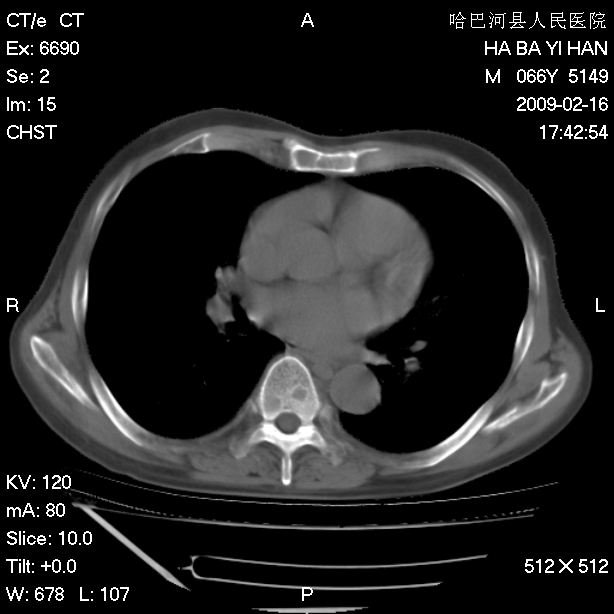

以下是引用huangxun4321在2009-2-16 20:18:00的发言:[br]部分病灶可见硬化边,部分可见骨质破坏消失,部分病灶内可见骨脊,说明病灶内既有良性病变,又有恶性病变,考虑骨巨细胞瘤恶变,未除骨纤恶变,畸形性骨炎少见,亦要考虑.

以下是引用731208在2009-2-16 20:31:00的发言:[br]考虑恶性胸膜间皮瘤并肋骨,脊柱转移。

以下是引用yijiansheng在2009-2-16 20:16:00的发言:[br]考虑恶性胸膜间皮瘤并肋骨,脊柱转移。

以下是引用形影不离在2009-2-16 19:55:00的发言:[br]考虑多发性转移瘤。